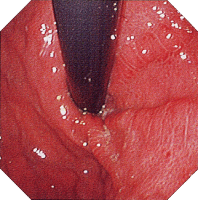

内視鏡所見

初期病変 アフタ様びらん アフタ様潰瘍

クローン病 クローン病画像 クローン病画像

提供:牧山和也先生